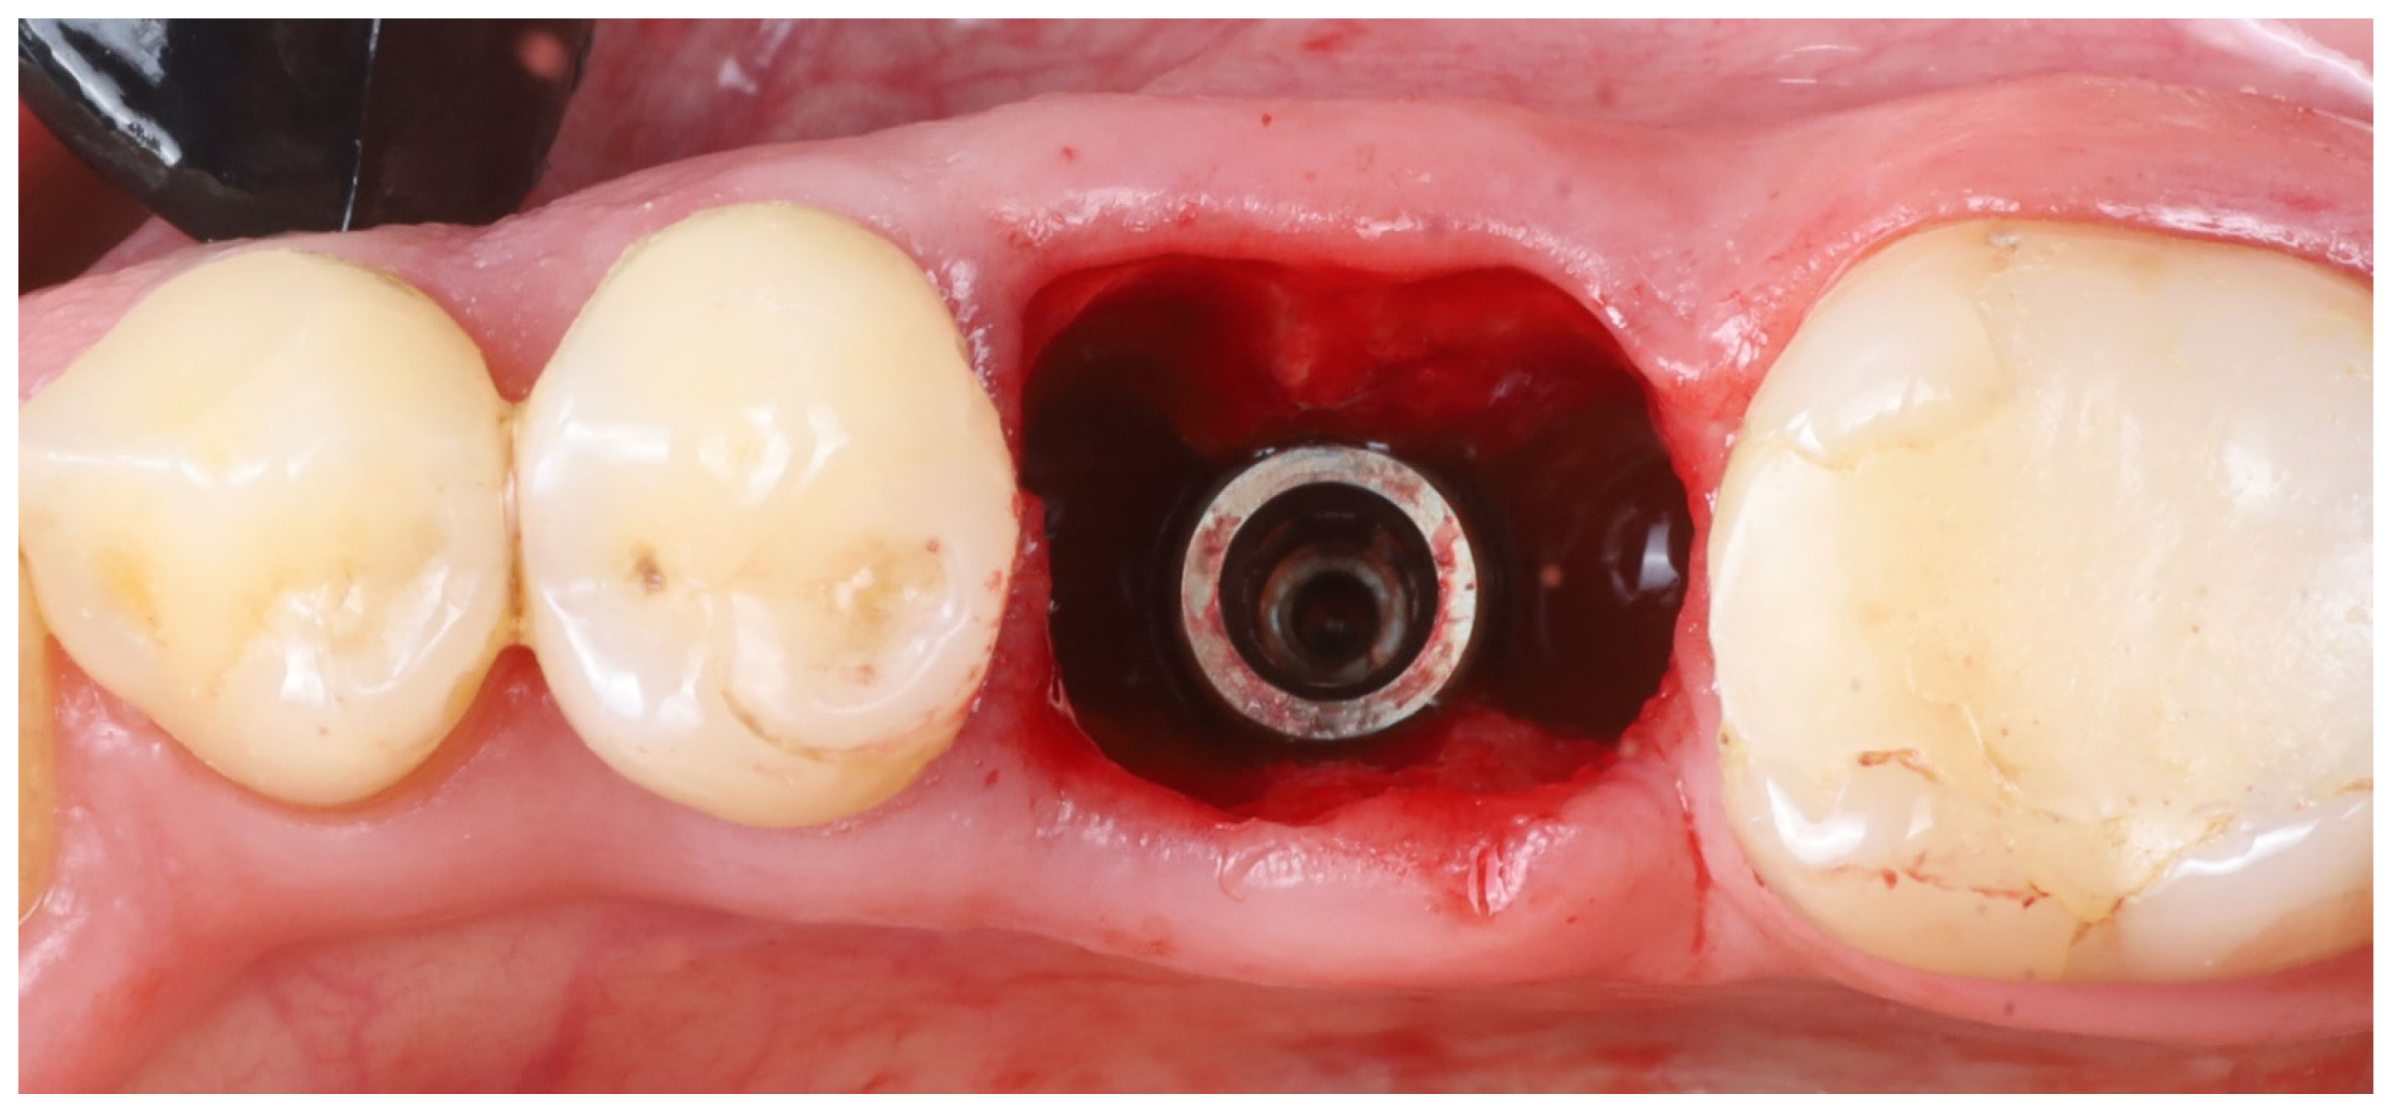

- 11.

- Implant placement: A dental implant (Megagen Blue Diamond, 4.8 mm diameter × 10 mm length, conical “Deep thread” design) was inserted into the prepared osteotomy. The implant was centered within the socket, with its shoulder positioned roughly 5–6 mm below the level of the surrounding gingival margin (Figure 4). The implant fits snugly between the two buccal shields without exerting undue pressure on them. Primary stability was achieved; the implant had an insertion torque of about 35 N·cm, and verification with a resonance frequency analysis device showed an Implant Stability Quotient (ISQ) exceeding 70. (This high primary stability indicated that the implant was well stabilized in the septal bone despite the immediate placement.)

- 12.

- Socket sealing with healing cap: The socket orifice was sealed with a large-diameter healing abutment instead of suturing a flap. A wide, 9 mm diameter, and 6 mm height standard healing cap was attached to the implant, which effectively covered the socket opening and conformed to the circumference of the socket (Figure 5). This approach is intended to protect the socket and support the surrounding gingival margins without requiring a flapped closure or graft. No additional bone graft or membrane was placed in the socket; a blood clot was allowed to fill the gaps between the implant and shields [17].